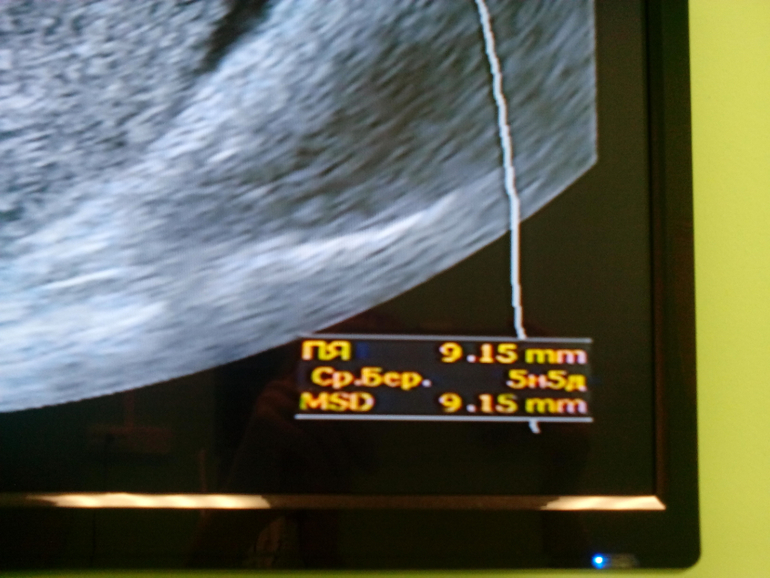

Пя в матке одно

Срок 5 акушерских недель и 5 дней